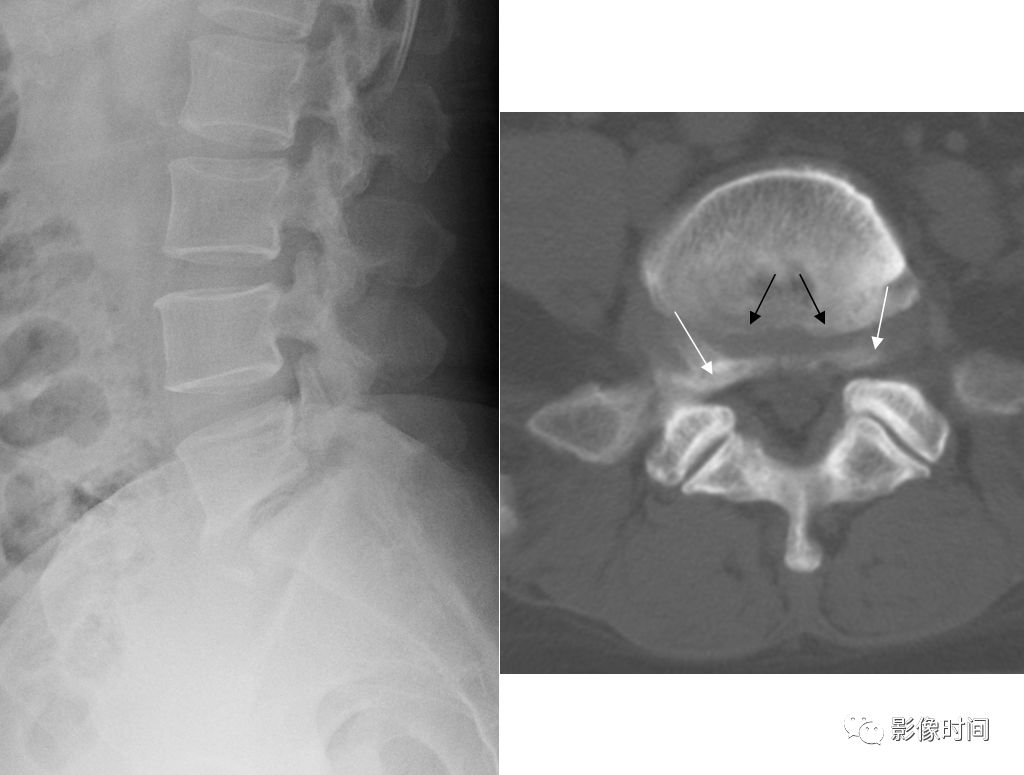

4斯科蒂狗征与狗戴项圈征

斯科蒂狗征(scottie dog sign)/ 猎犬项圈征

斯科蒂狗征,亦有译为苏格兰狗征。是指在斜位 X 线片上腰椎正常结构的投影,横突、小关节突、椎弓根投影构成了酷似斯科蒂狗的轮廓,故而得名。当椎弓狭部裂时,「狗颈部」会出现透亮带,酷似「狗戴上了项圈」,即为狗戴项圈征(也有称为断颈或斩首征的)。

典型病例

两例腰椎椎弓狭部裂。斜位 X 线片示椎弓狭部骨质不连续,可见透亮带影(箭示),呈现狗戴项圈征。

引用自:https://radiopaedia.org/articles/scottie-dog-sign-spine